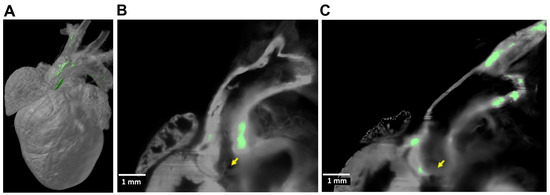

- Bridoux, J.; Neyt, S.; Debie, P.; Descamps, B.; Devoogdt, N.; Cleeren, F.; Bormans, G.; Broisat, A.; Caveliers, V.; Xavier, C.; et al. Improved Detection of Molecular Markers of Atherosclerotic Plaques Using Sub-Millimeter PET Imaging. Molecules 2020, 25, 1838. [Google Scholar] [CrossRef] [PubMed]

- Creager, M.D.; Hohl, T.; Hutcheson, J.D.; Moss, A.J.; Schlotter, F.; Blaser, M.C.; Park, M.A.; Lee, L.H.; Singh, S.A.; Alcaide-Corral, C.J.; et al. (18)F-Fluoride Signal Amplification Identifies Microcalcifications Associated With Atherosclerotic Plaque Instability in Positron Emission Tomography/Computed Tomography Images. Circ.-Cardiovasc. Imaging 2019, 12, e007835. [Google Scholar] [CrossRef]

- Florea, A.; Sigl, J.P.; Morgenroth, A.; Vogg, A.; Sahnoun, S.; Winz, O.H.; Bucerius, J.; Schurgers, L.J.; Mottaghy, F.M. Sodium [(18)F]Fluoride PET Can Efficiently Monitor In Vivo Atherosclerotic Plaque Calcification Progression and Treatment. Cells 2021, 10, 275. [Google Scholar] [CrossRef]